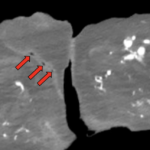

Fournier’s gangrene is a well-established surgical emergency as patients can decompensate rapidly, resulting in significant morbidity and mortality. We describe a case in which a 54-year-old medically complex male presented to the emergency department (ED) with a primary complaint of abdominal pain after a therapeutic paracentesis was performed by interventional radiology just prior to arrival. Upon further questioning, the patient reported scrotal pain that had developed over three to four days. On exam, the patient was well-appearing although he did have scattered scrotal masses with chalky white purulence. Given the relatively quick development, an atypical presentation of Fournier’s gangrene was suspected, and the patient was started on antibiotics with urology immediately consulted. Imaging was concerning for subcutaneous gas. The patient was subsequently taken to the operating room (OR) for debridement, where Fournier’s gangrene was confirmed by surgical investigation and culture. Significant lessons from the case include the importance of early identification of Fournier’s gangrene and having a low threshold to start treatment in coordination with a surgical service for atypical presentations.